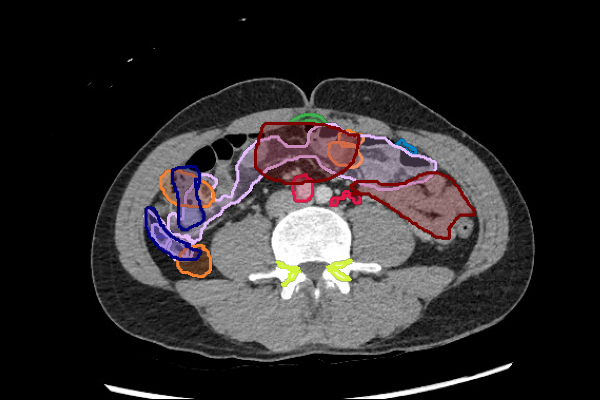

Mass or Adenopathy

Infection or Inflammation

Obstruction